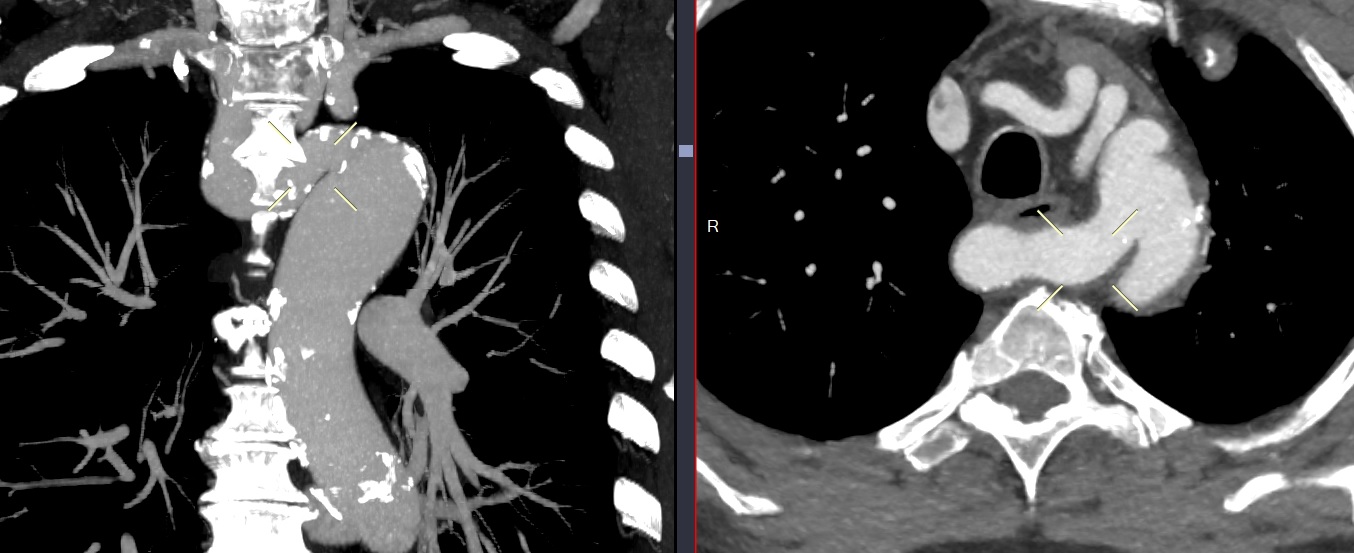

Double arc aortique

- Malformation symptomatique la plus fréquente

- Compression trachéale avec symptomes respiratoires++

- Double compression de l’oesopage en “Reverse S” sur la TOGD typique

Double arc aortique avec segment atrésique